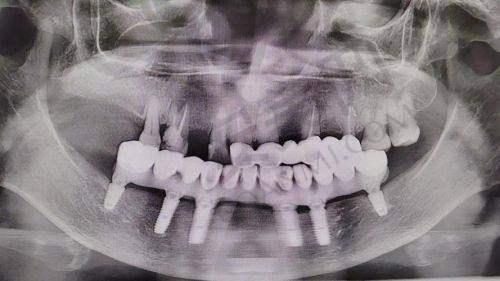

all - on - 4半口种植牙是一种精良的牙齿种植技术。它通过在牙槽骨内植入4颗种植体,然后利用这4颗种植体支撑起半口的牙桥。与传统的种植牙技术相比,all - on - 4半口种植牙具有诸多优势。首先,它大大减少了种植体的植入数量,降低了手术的创伤和风险。其次,手术时间相对较短,患者的修复时间也更快。此外,这种技术能够在当天完成种植和修复,让患者尽快修复牙齿的咀嚼功能和美观度。